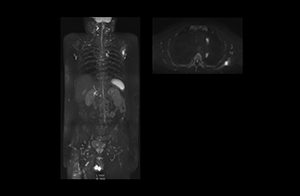

After implementing the improved whole body protocol, the radiology team initially did not see a large increase in referrals, although Dr. Nobusawa saw clinical cases where the DWIBS images provided him valuable information for diagnosis. This is why Dr. Nobusawa and Mr. Naka started to actively educate referring physicians about the value of whole body DWIBS. They organized several presentations for physicians in the hospital, where they explained how DWIBS can be of value in oncology patients. The information it provides can be useful for physicians when staging cancer, as well as when determining or adjusting treatment strategy. Mr. Naka remembers some cases where DWIBS provided remarkable information. “In one example, DWIBS visualized bone lesions that could not be seen on PET or SPECT. In another case we had found a bone lesion when a normal L-spine scan for narrowing of the disk space was done. One extra DWIBS scan (2 stations, 8 minutes) demonstrated a lesion that later was confirmed to be the primary region of cancer.”

In certain cases, radiologists now choose DWIBS to make diagnoses that used to depend on nuclear medicine studies. “We don’t have SPECT or PET in our hospital, so for instance for visualizing metastasis and monitoring the effect of treatments such as chemotherapy or radiotherapy, we used to refer patients outside the hospital. Now, these patients are sent to MRI for our whole body protocol with DWIBS,” Mr. Naka says.